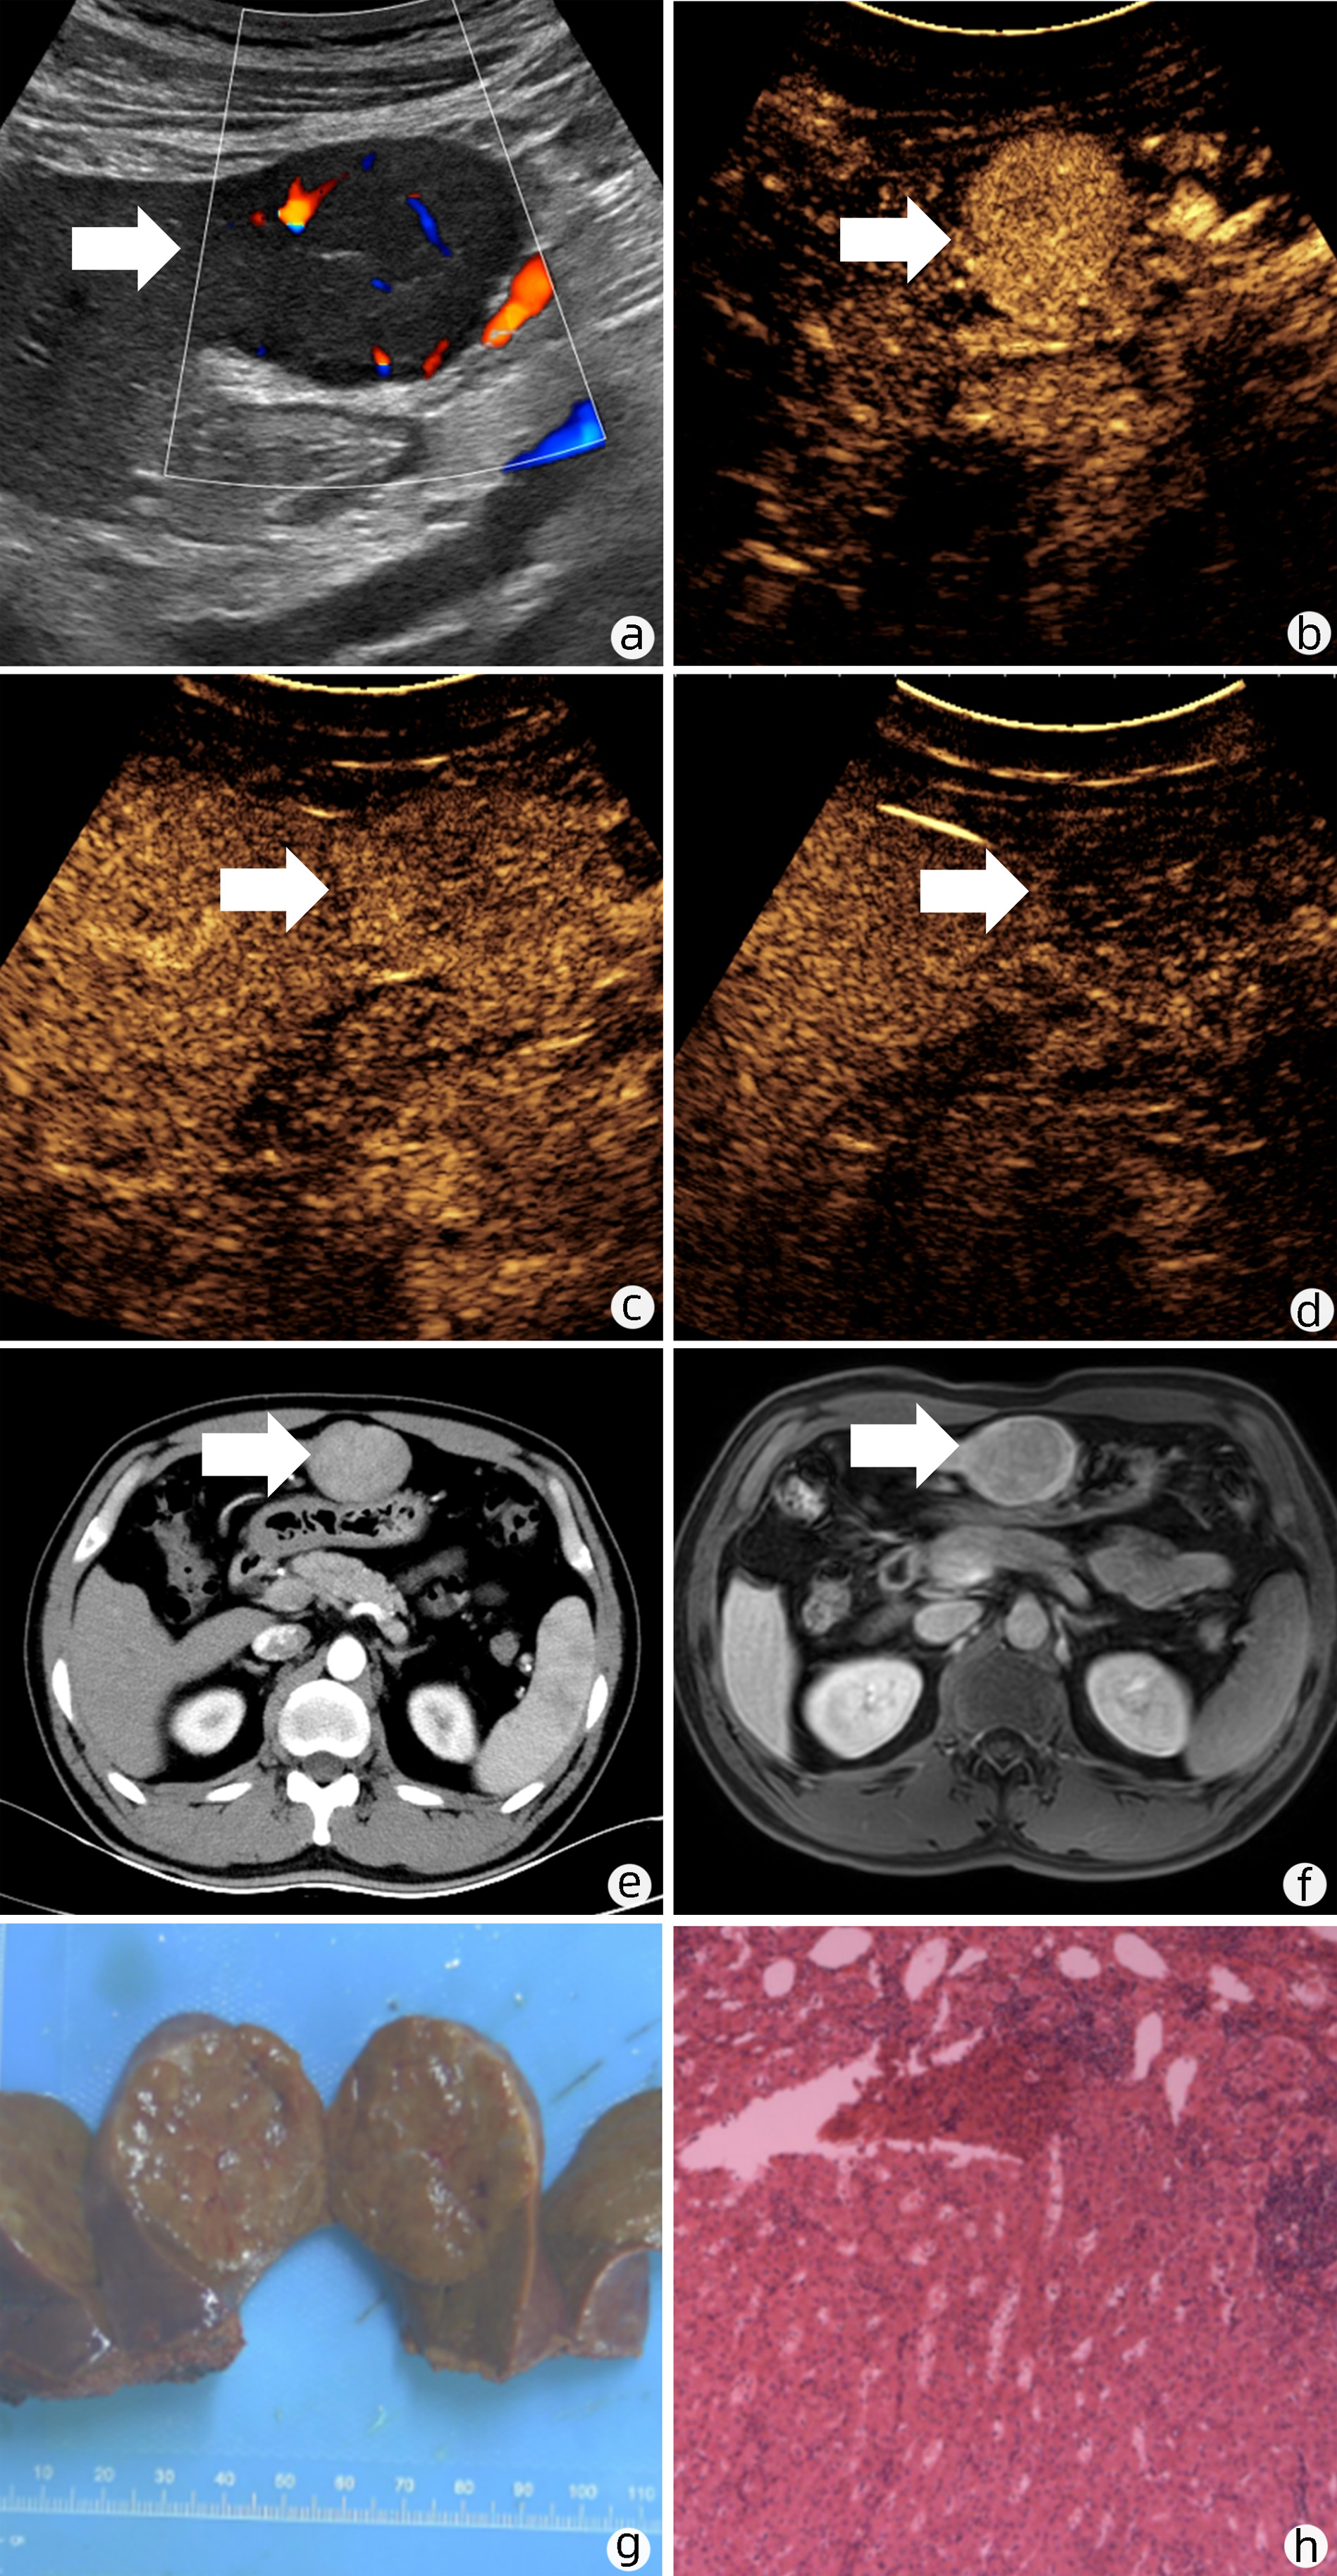

Focal nodular hyperplasia-like nodules in liver cirrhosis: An imaging analysis of three cases

Zinan LI, Shaoshan TANG, Xingni WU, Xiang LI

2023, 39(1): 142-146. DOI: 10.3969/j.issn.1001-5256.2023.01.021

Abstract(2471) HTML (2381) PDF (3394KB)(133)